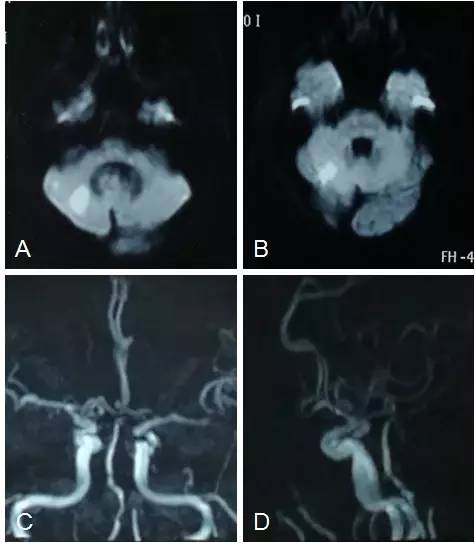

入院前,在当地医院行头颅磁共振检查:右小脑半球梗死(图1A,B),左椎动脉发出PICA以远闭塞,右椎动脉V4段远段及基底动脉中段见局限性中度狭窄(图1C,D)。在当地给予双联抗血小板等治疗后患者仍遗留活动后头晕症状,为寻求进一步治疗收入院。

图1